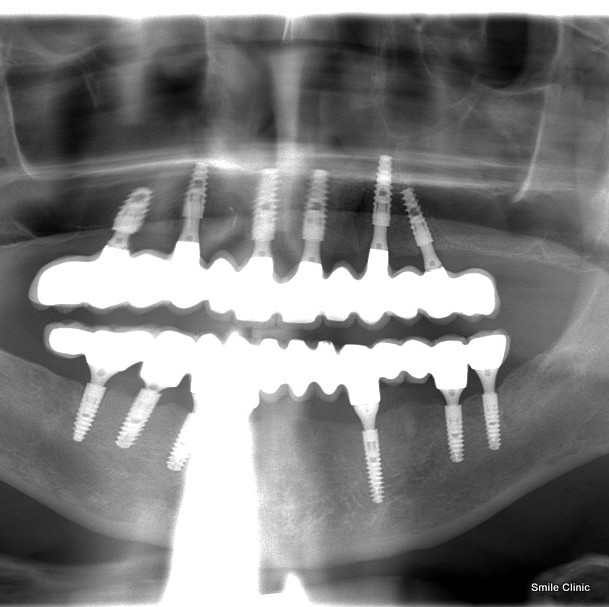

Andy from Cheshire came to us for dental implants to his lower jaw that was completed back in 2013.

It was great to see Andy again, this time to restore his upper jaw with 6 dental implants supporting 12 crowns on a bridge.